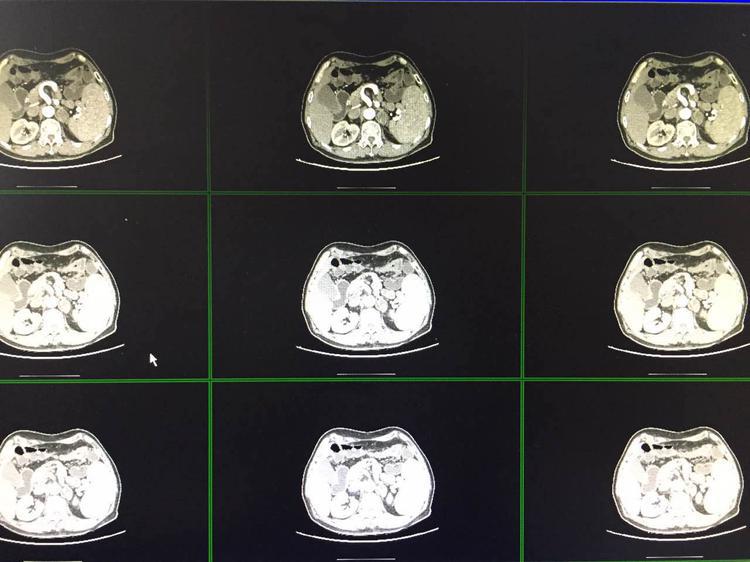

患者男性,66岁,主因“发现左肾上腺占位7入院。CT检查示:左侧肾上腺腺瘤,大小约3.3*2.2cm,肾上腺相关血化验指标均正常,考虑为无功能腺瘤。向患者及其家属交待病情,遂于2017年07月06日在全麻下了3D腹腔镜下左侧肾上腺腺瘤切除术,术后病理回报:肾上腺皮质腺瘤,患者恢复可,现已出院。